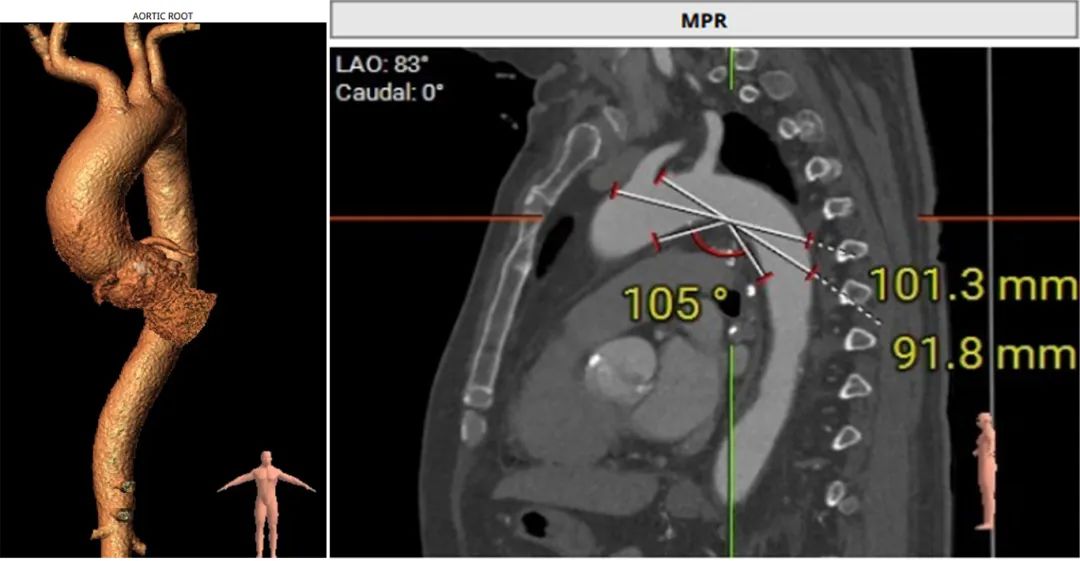

CT分析:

术前CT分析判断该心耳为反鸡翅型左心耳,选择偏下略偏前的位置进行房间隔穿刺。在工作体位造影后,可见左心耳内梳状肌发达,反鸡翅叶显影清晰,鞘管轴向佳。经DSA测量左心耳开口18mm深度17mm,结合TEE测量数据,综合考虑选用WATCHMAN24mm封堵器进行封堵。在展开封堵器时利用在体内借深度技巧,保证封堵器封堵位置合理。封堵器展开后经造影检查封堵器封堵效果理想,牵拉试验稳定。超声评估封堵器各角度无残余分流,位置理想,满足PASS原则,随即释放封堵器,一站式手术顺利结束。